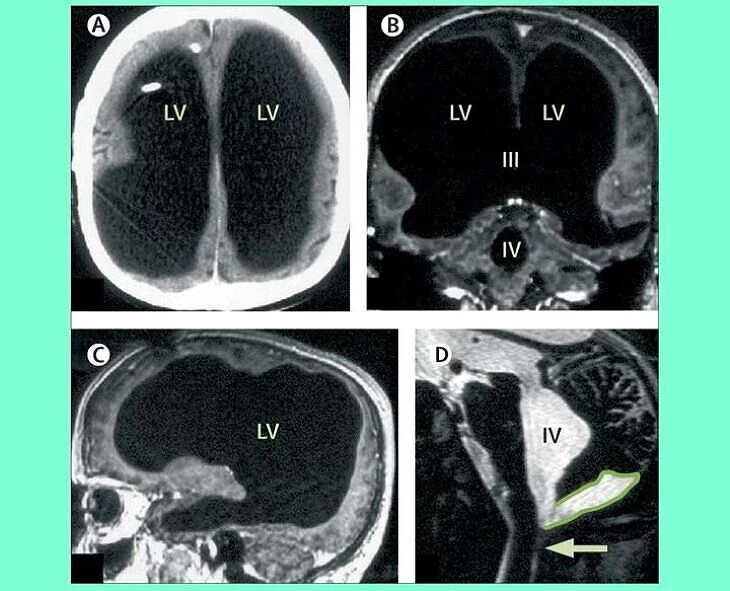

మెదడులో 90శాతం ఖాళీ.. కానీ!

ఫ్రెంచ్కు చెందిన 44ఏళ్ల వ్యక్తి మెదడు 90శాతం ద్రవంతో నిండిపోయింది. అయినప్పటికీ ఆయనకున్న తెలివితేటలు, సాధారణ జీవితం గడపడాన్ని చూసి శాస్త్రవేత్తలు సైతం ఆశ్చర్యపోయారు. 2007లో ఆయన తీసుకున్న ఓ స్కానింగ్లో ఈ విషయం బయటపడింది. పెళ్లయి, ప్రభుత్వ ఉద్యోగం చేస్తున్న ఆయనకు చిన్నప్పుడు వచ్చిన ‘హైడ్రోసెఫాలస్’ వల్ల మెదడు కుంచించుకుపోయింది. ఇలాంటి ఇంట్రెస్టింగ్ విషయాలు ‘వంద రోజుల్లో-వంద వింతలు’లో (33/100)